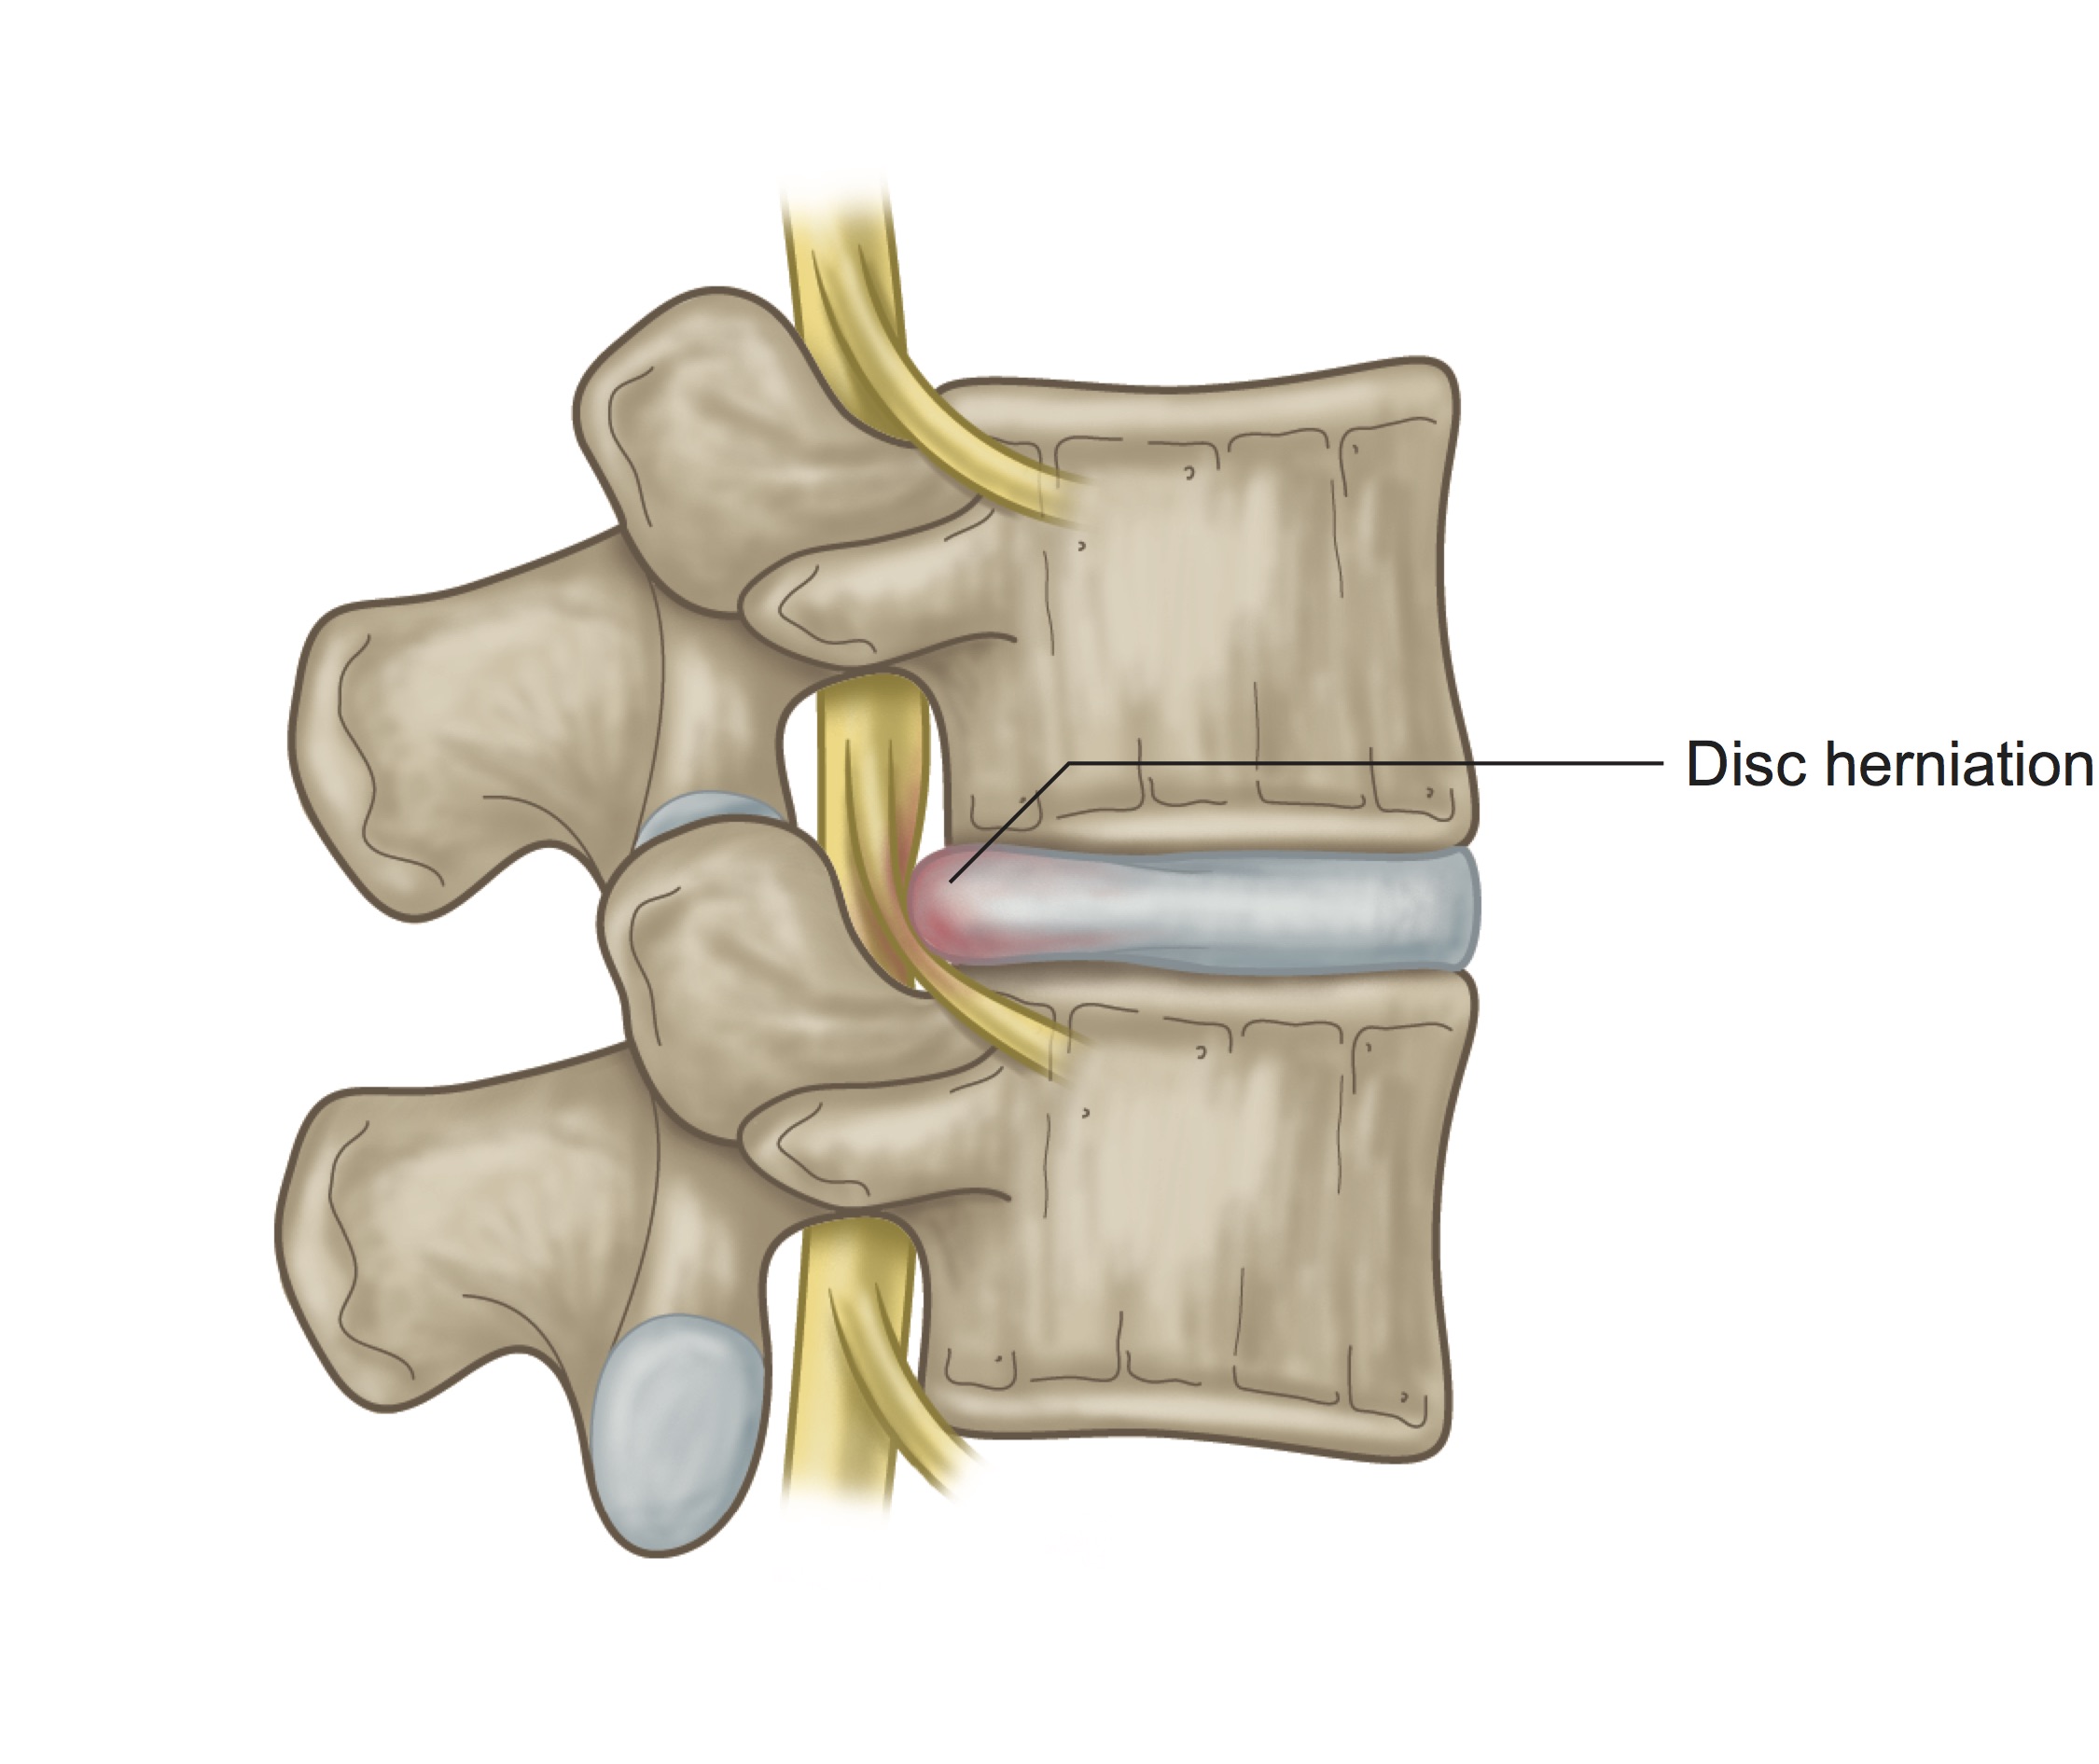

Herniated Disc | Causes, Symptoms, Treatments – Ainsworth Institute

Bulging and Herniated Discs – Explained | Physical Health Care

What is the difference between a bulging disc and a herniated disc?

Herniated, Bulging or Slipped Discs – SOS Chiro